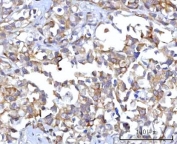

IHC staining of FFPE human gastric adenocarcinoma tissue with RAP1GAP antibody. HIER: boil tissue sections in pH8 EDTA for 20 min and allow to cool before testing.